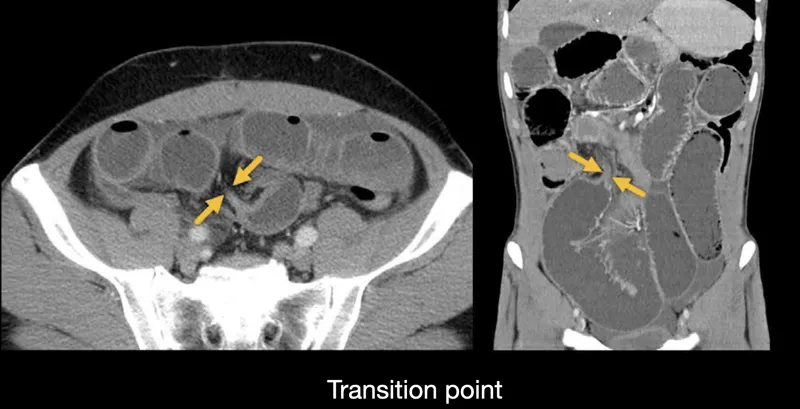

| Bowel obstruction | Colicky pain, distension, vomiting, tinkling bowel sounds | AXR (dilated loops), CT (transition point) | <2h if ischaemia suspected |

- Imaging: Erect CXR (perforation), AXR (obstruction), USS (biliary/gynae)